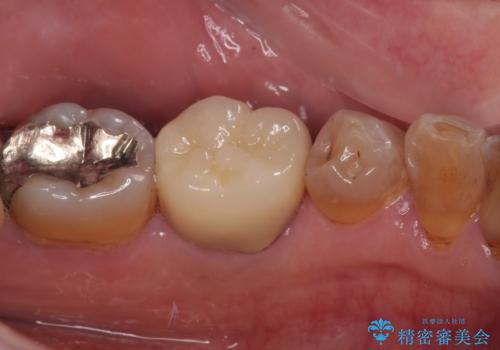

まずは根管治療を行い、症状が消退したことを確認してオールセラミッククラウンにて補綴治療を行うこととしました。

根管治療を行った奥歯は、再発防止や残された歯質を守るため、クラウンによる補綴治療が必要となります。

補綴後6ヶ月経過しレントゲンを撮影したところ、根尖周辺の病変が消失していることが確認できました。